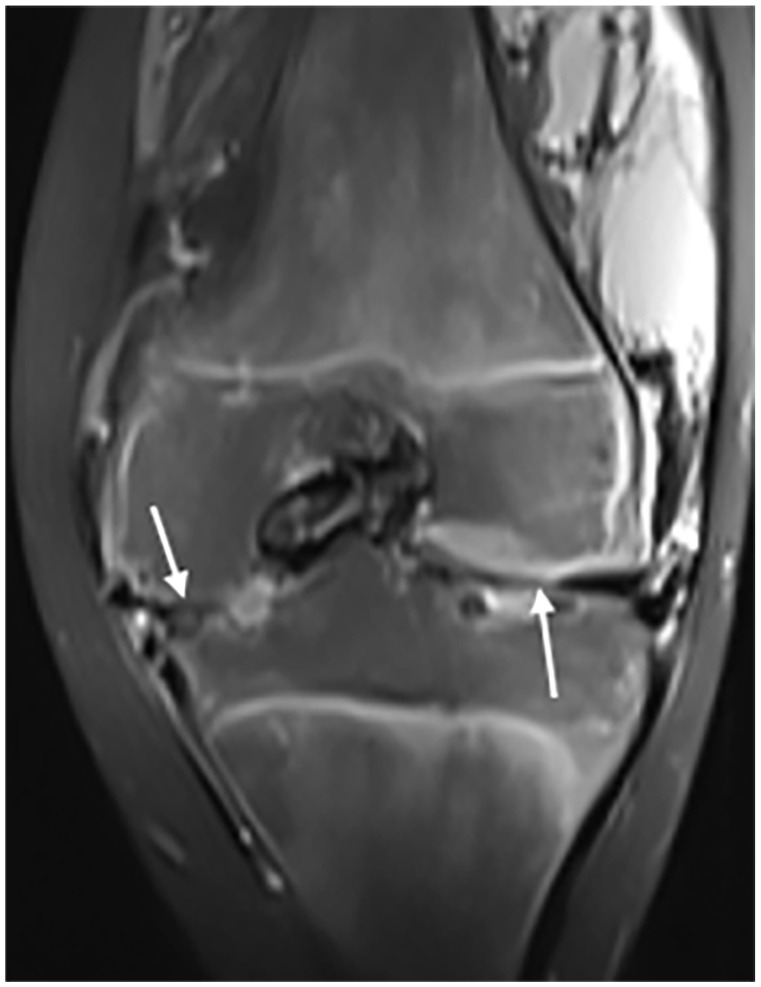

Hemophilia is a congenital coagulopathy characterized by a deficiency of coagulation factors and the development of haematomas and haemarthrosis, either spontaneously or after minor trauma. Recurrent joint hemorrhage in hemophilia patients leads to progressive and degenerative arthropathy, which affects around 90% of patients with severe disease and contributes significantly to disease morbidity. Positive diagnosis is based on biology. Imaging, particularly MRI, plays an essential role in assessing the evolution and complications, especially osteoarticular complications. We report 2 cases of severe hemophilia A, who presented with almost identical clinical and radiological symptoms. The patients developed severe arthropathy with a course marked by recurrences of haemarthrosis.

Abstract Image